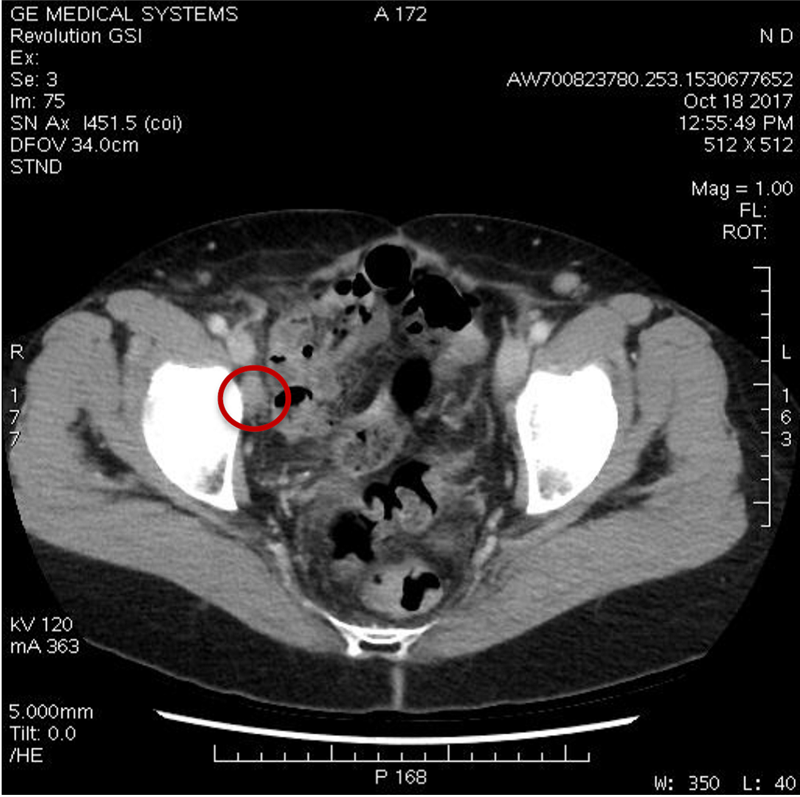

Among the five patients who were evaluable for efficacy as of June, three achieved stable disease after two cycles of Cantrixil monotherapy. One the three subsequently went on to achieve a partial response after being treated with Cantrixil in combination with chemotherapy. Exhibits 1 and 2 show the dramatic reduction in the size of the tumor (circled in red) in the partial responder over the course of the study.

Exhibit 1: Tumor seen at baseline in October 2017…

Exhibit 2: …had shrunk markedly by the end of study participation in May 2018

Source: Kazia investor presentation, July 2018